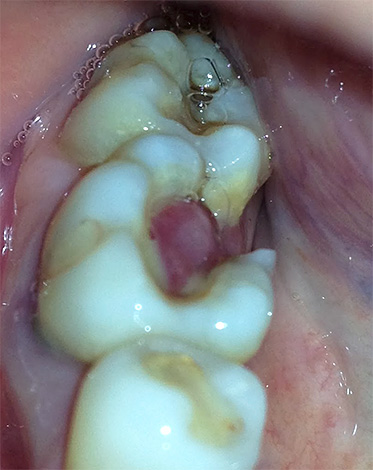

Nel tempo, il flusso può trasformarsi in una fistola (vedi foto):

Nelle forme croniche di parodontite, le formazioni più spiacevoli sulla gomma sono le fistole. Questi sono canali che si allontanano dalla radice infiammata del dente e da cui esce periodicamente un pus maleodorante, facilitando la sofferenza di una persona.